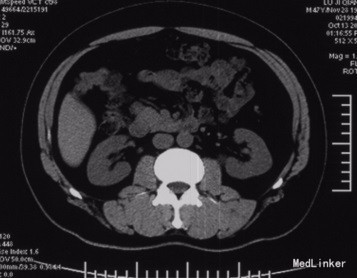

查体:神清,腹软,未及包块,无压痛及反跳痛,神经系统检查未见异常 辅查:外院头颅CT平扫:腔隙性脑梗;胰腺CT平扫:胰头、十二指肠降部稍低密度影,肝内多发小囊肿;上腹部增强CT:胰腺低密度影,考虑良性;肝内多发小囊肿。 入院检查:血、尿、粪常规、肝肾功能、电解质、凝血功能正常;AFP、CEA、CA19-9、CA125、CA15-3、CA72-4均正常;胰岛素78.33mIU/L,C肽 4.91ug/L。腹腔动脉DSA:胰头区富血供肿瘤; 胰腺增强MRI:1、胰头部富血供病变,考虑胰岛素瘤可能性大;2、肝内多发小囊肿。

术前诊断:1、胰头占位性病变(胰岛素瘤?),2、腔隙性脑梗塞,3、肝内多发小囊肿。 术后诊断:1、胰头胰岛素瘤,2、腔隙性脑梗塞,3、肝内多发小囊肿。 入院后控制血糖,完善相关检查在腹腔镜下行胰岛素瘤切除术,术中为、十二指肠、胆囊、横结肠未见异常,胆总管无扩张,打开胃结肠韧带,于胰头健可见大小约2*2cm肿块,表面光滑,边界清,突出于表面,遂行胰岛素瘤切除术超声刀沿肿块边缘完整切除肿块,检查未伤及主胰管。 术后监测血糖,行抗炎、抑酸、补液等对症支持治疗,复查C肽及胰岛素均正常,空腹血糖值正常,康复后出院。